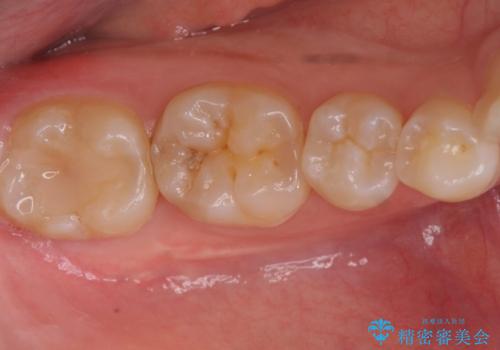

セラミック治療 → セラミックインレー

歯と歯の間によくものが詰まる。。セラミック治療

銀の詰め物を白い物にしたい